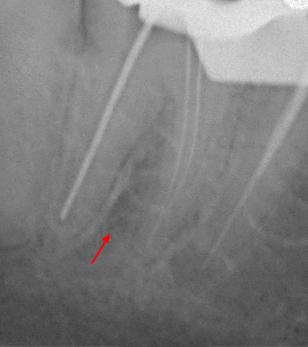

Пациентка 28 лет обратилась с жалобами на приступообразную ночную боль в области нижней челюсти справа.

На жевательной поверхности 47 зуба глубокая кариозная полость в пределах околопульпарного дентина, пульповая камера не вскрыта, зондирование болезненное, перкуссия безболезненная, холодовой тест резко болезненный, после удаления раздражителя болевая реакция продолжается в течении 20-ти секунд.

Диагноз: необратимый пульпит 47-го зуба.

На рентгенологических снимках представлена картина до лечения, диагностический снимок и конечный результат.